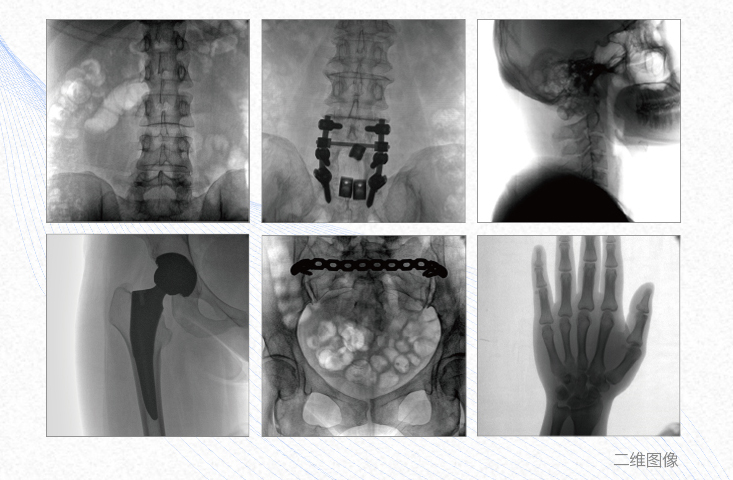

1、脊柱外科

有效重建復(fù)雜的脊柱三維模型,提供準(zhǔn)確的二維、三維圖像,提高螺釘植入的準(zhǔn)確性,縮短手術(shù)時(shí)間,減少并發(fā)癥的概率,降低輻射的攝入。

2、創(chuàng)傷外科

例如骨盆骨折內(nèi)固定術(shù),可術(shù)中三維重建髖臼關(guān)節(jié)面,準(zhǔn)確定位并植入螺釘,有效縮短螺釘植入的時(shí)間和透視暴露時(shí)間,減少術(shù)中及術(shù)后并發(fā)癥發(fā)生的概率。

3、關(guān)節(jié)外科

主要應(yīng)用于肩關(guān)節(jié)、肘關(guān)節(jié)、髖關(guān)節(jié)、膝關(guān)節(jié)的關(guān)節(jié)置換及解剖復(fù)位的定位。它可以準(zhǔn)確地置入假體,減少輻射時(shí)間,降低輻射劑量。

4、截骨矯形外科

例如治療先天性脊柱側(cè)后凸畸形,可有效引導(dǎo)術(shù)者植入后路螺釘并切除半錐體,達(dá)到滿(mǎn)意的截骨矯正效果。